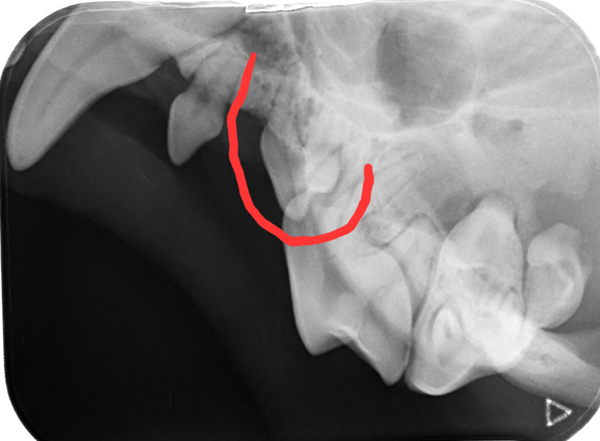

Das wahre Ausmaß zeigte sich allerdings erst nach ausführlicher Untersuchung in Narkose. Das Dentalröntgen und die Sondierung zeigten, dass bereits große Teile des Kieferknochens durch die Parodontitis verursachenden Bakterien zerstört wurde (die gelbe Linie zeigt an, wo der Kieferknochen sien sollte, die rote zeigt an wieviel Knochen bereits zerstört wurde). Dieser Knochenschwund ist leider irreversibel und in diesem Endstadium hilft nur noch die Extraktion.